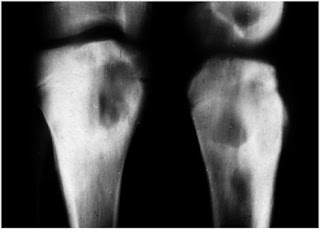

Osteomielite acuta ematogena nei bambini

Ragazzo, 15 anni

Osteomielite dopo una ferita di un dito:

Sclerosi e retrazione periostea